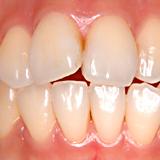

セラミックの歯で審美 | ||

| 矯正する時間がない患者さんの前歯二本をセラミックの歯で審美的に改善しました。(右上一本だけでは右上の歯だけが小さくなります) |

【術前】 |

【術後】 |